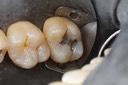

Alan Chinn #5 prep